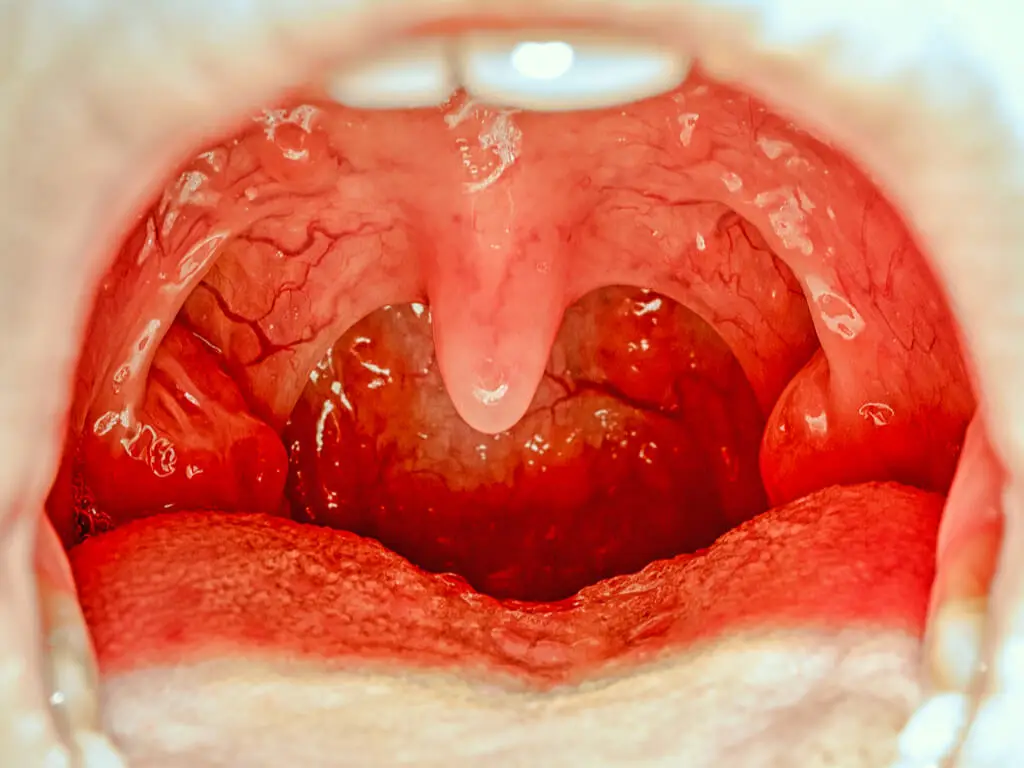

El paladar es la parte superior de la cavidad bucal. Tiene como función separar la boca de la nariz, lo que permite el proceso de alimentación. Se divide en dos partes: el superior o duro (hecho de hueso) y el posterior o blando (hecho de tejido). Ahora bien, ¿qué hacer cuando sufrimos una quemadura en el paladar?

Puesto que tiene muchas terminaciones nerviosas, fácilmente puede generar molestia o dolor cuando se lesiona. Pero no te preocupes porque a continuación te contaremos cómo puedes aliviar las molestias en caso de que te quemes bebiendo o comiendo algo demasiado caliente.